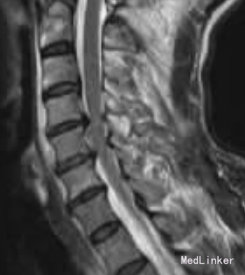

查体:C4-C6棘突压痛明显,活动受限,稍有肿胀,双上肢感觉麻木伴有痛觉过敏,双侧肱二头肌肌力Ⅳ级,双手握力下降,双 下肢感觉活动可,肢端感觉血供可。 辅助检查:MRI检查显示C3-C4椎间盘后突伴凸C4-C6平面椎管狭窄,颈髓受压,髓内见小片高信号影,颈椎退行性改变。

诊断:1.颈椎病;2.颈髓损伤。 手术:采用全身麻醉,取颈部右侧斜行切口,长约6cm,逐层切开皮肤、颈阔肌,沿气管食管与胸锁乳突肌、颈动静脉鞘间隙分离暴露椎前筋膜,分离 椎体前筋膜,摄定位X线片,将前纵韧带切开,显露病变椎体及椎间盘, 先用角度刮匙和髓核钳切除病变段椎间盘及上下终板,用高速磨钻行病变椎体大部分切除,显露硬脊膜和致压物。 小心分离致压物,彻底解除脊髓压迫。 植入大小适中填满松质骨的钛网, 再将长短合适的颈前路钢板系统通过螺丝钉固定于开槽减压区上下方椎体上。C形臂X线机透视证实钢板系统位置正确后,切口内置负压引流管,逐层缝合切口。 术后第5天突发神志不清,躁动不安,查体:双上肢肌 力Ⅲ级,双下肢肌力O级,病理反射未引出。 急查头颅CT、血电解质、血气分析等均未发现明显异常, 胸部CT示双肺下叶炎症伴两侧胸膜反应。 经相关临床科室会诊后转入ICU监护,予抗感染,加强龙冲击等对症支持治疗。复查头颅MRA,胸腰椎MRI均未见明显异常,颈椎MRI示:C4-C6椎体内固定术后改变,颈髓受压,髓内见小片高信号影。经全科讨论:颈髓受压影像考虑为内固定产生伪影所致。 术后第10天,患者情况较前明显好转,转入我科继续抗感染、营养神经、针灸等对症治疗。术后20d双下肢肌群肌力恢复至Ⅲ级水平。术后45d双上肢肌群肌力Ⅴ级,双下肢肌群肌力Ⅵ级强,已下地步行训练。